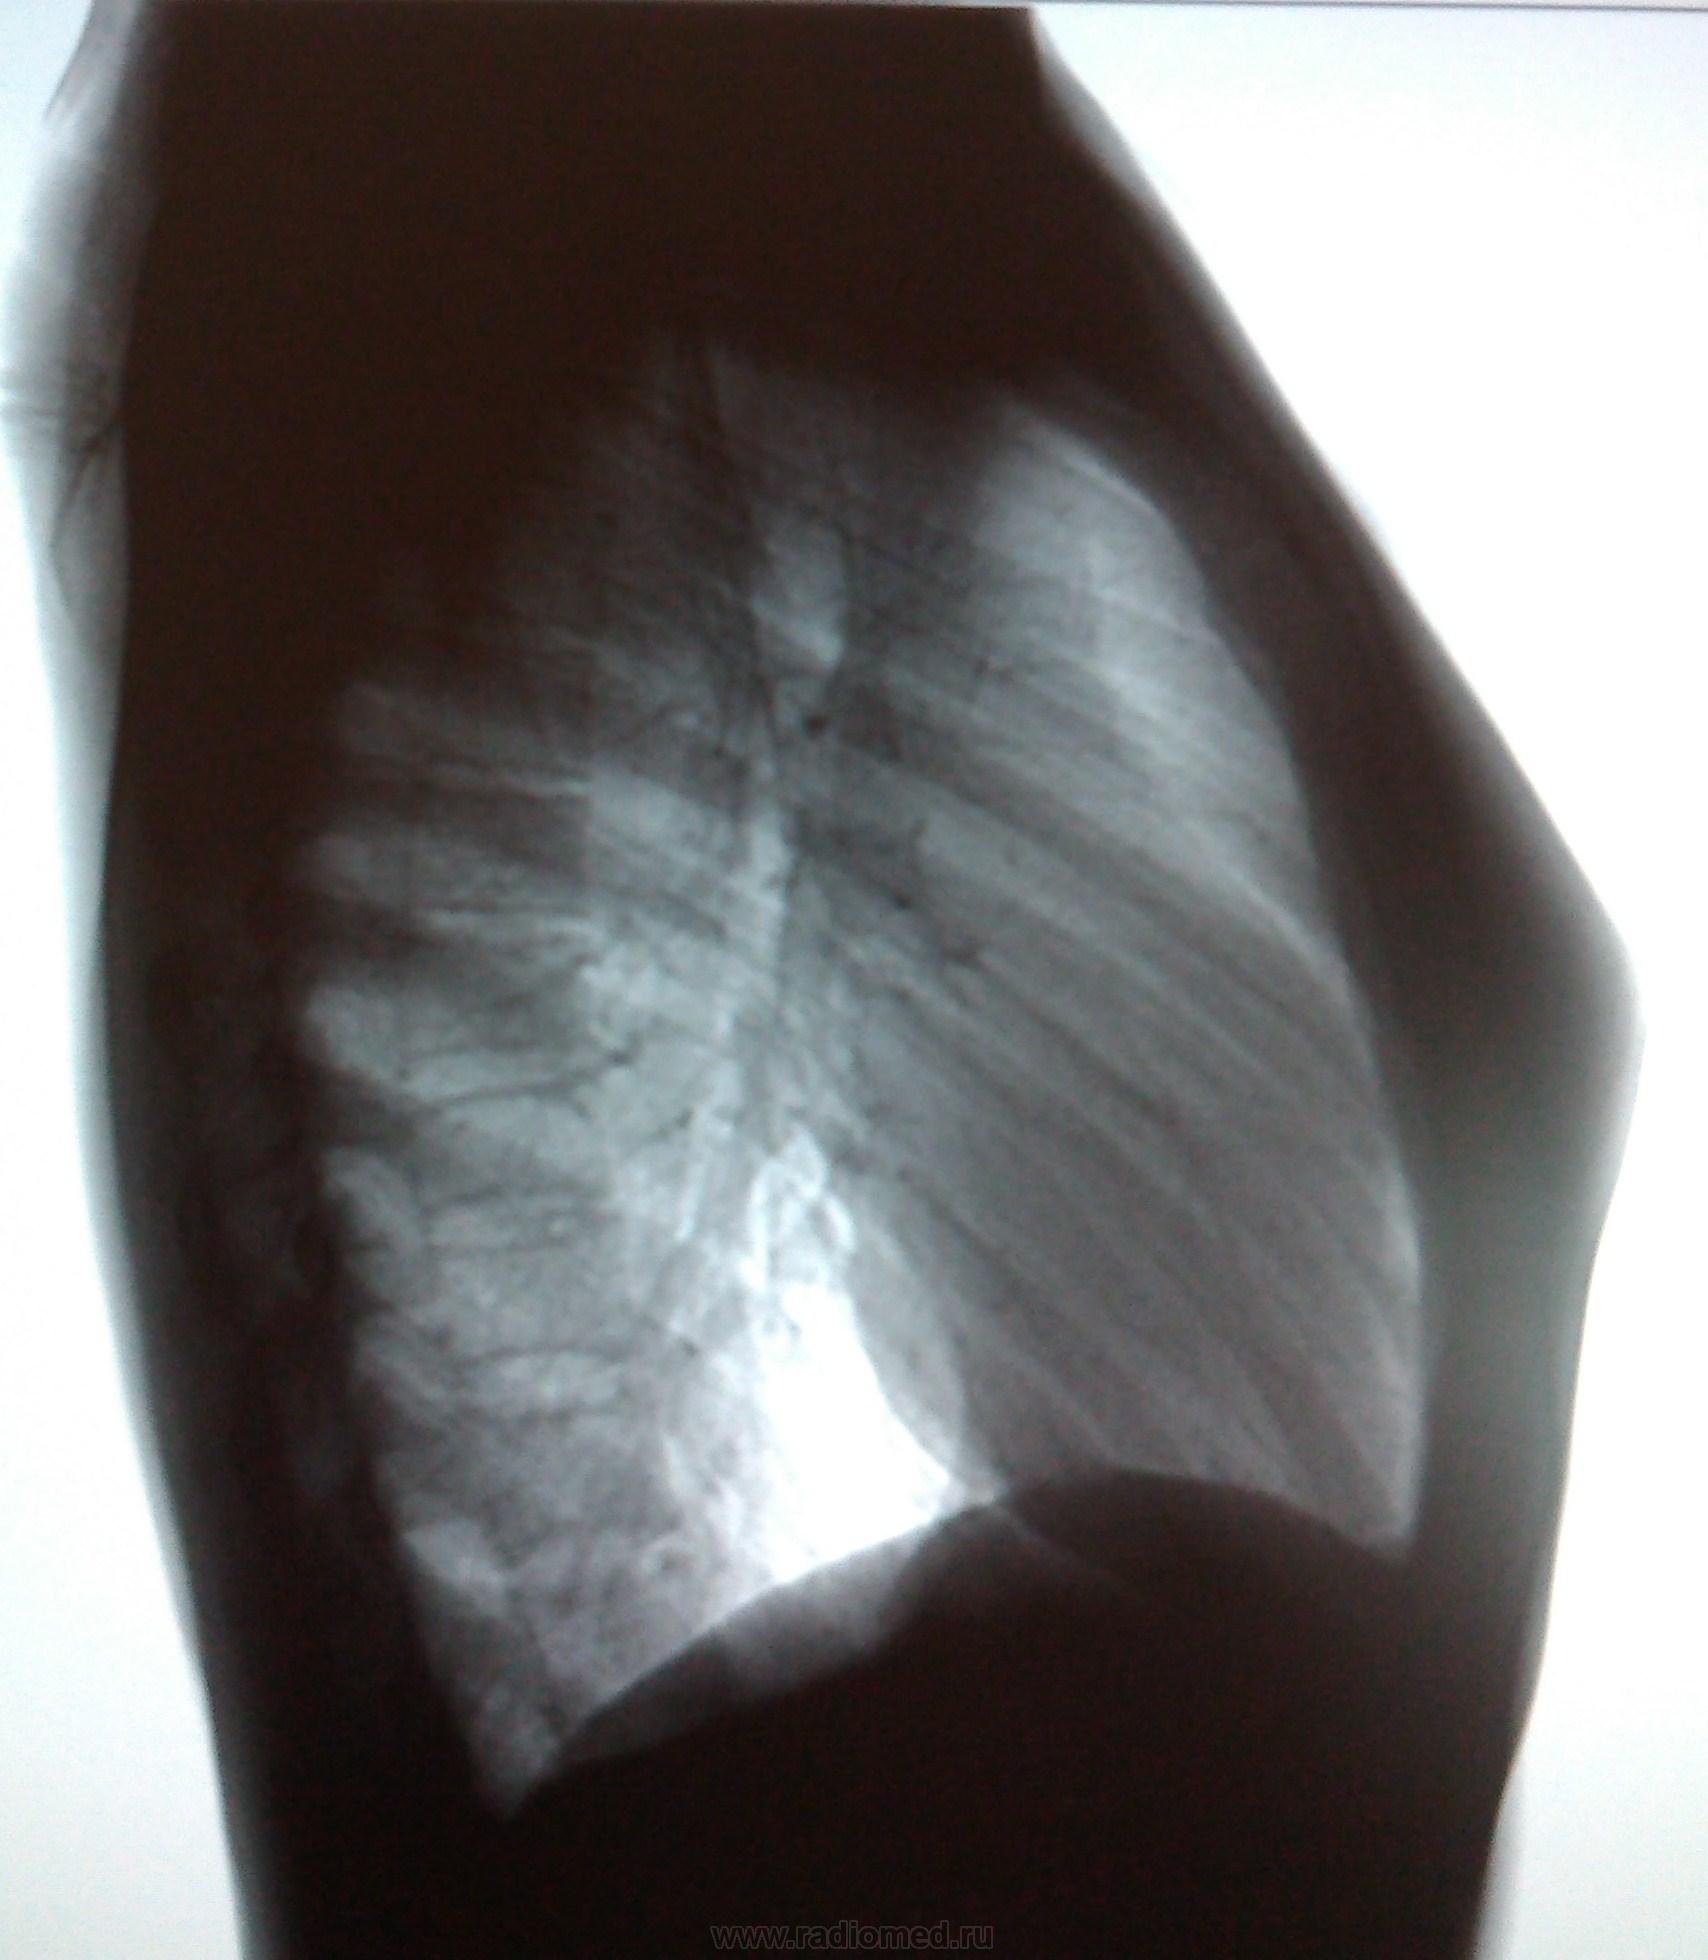

Пол пациента: Женский пол Тип патологии: Другое Область исследования: Грудная клетка и верхние дыхательные пути Методы исследования: Rg Пациентка, 22 года. Мед. осмотр. https://radiomed.ru/sites/default/files/styles/case_slider_image/public/user/18609/img_20130821_111923.jpg?itok=CBCcY0bh ID:30974 Ср, 21/08/2013 - 18:17 #1 Сергей Кузьминов Не на сайте Был на сайте: 1 год 2 месяцев назад Зарегистрирован: 06.10.2012 - 15:51 Публикации: 11813 Обе верхушки томографировать по поводу очаговых теней. Ср, 21/08/2013 - 19:06 #2 maker4ik Не на сайте Был на сайте: 8 лет 9 месяцев назад Зарегистрирован: 19.10.2011 - 17:49 Публикации: 2682 Не вижу патологии. Ср, 21/08/2013 - 21:36 #3 Dr. X-ray Не на сайте Был на сайте: 9 лет 8 месяцев назад Зарегистрирован: 19.07.2013 - 21:06 Публикации: 505 а средостение в верхнем отделе справа не расширено? Ср, 21/08/2013 - 22:20 #4 Сергей Кузьминов Не на сайте Был на сайте: 1 год 2 месяцев назад Зарегистрирован: 06.10.2012 - 15:51 Публикации: 11813 ИМХО Доля непарной вены.А очагульки не получается что-то пометить в пайнте. Ср, 21/08/2013 - 22:57 #5 Nikolas Не на сайте Был на сайте: 1 месяц 26 минут назад Зарегистрирован: 21.12.2010 - 20:37 Публикации: 4560 лимфомы Ходжкина необходимо исключить в первую очередь у молодой женщины. О верификации диагноза прошу сообщить на сайт. Чт, 22/08/2013 - 06:52 #6 Глазков Игорь А... Не на сайте Был на сайте: 11 месяцев 1 неделя назад Зарегистрирован: 19.12.2008 - 20:41 Публикации: 1597 напоминает лимфогранулёматоз. В верхушках лёгких ничего плохого не увидел. Прийди к Себе

Обе верхушки томографировать по поводу очаговых теней.

а средостение в верхнем отделе справа не расширено?

ИМХО Доля непарной вены.А очагульки не получается что-то пометить в пайнте.

лимфомы Ходжкина необходимо исключить в первую очередь у молодой женщины. О верификации диагноза прошу сообщить на сайт.

напоминает лимфогранулёматоз. В верхушках лёгких ничего плохого не увидел.